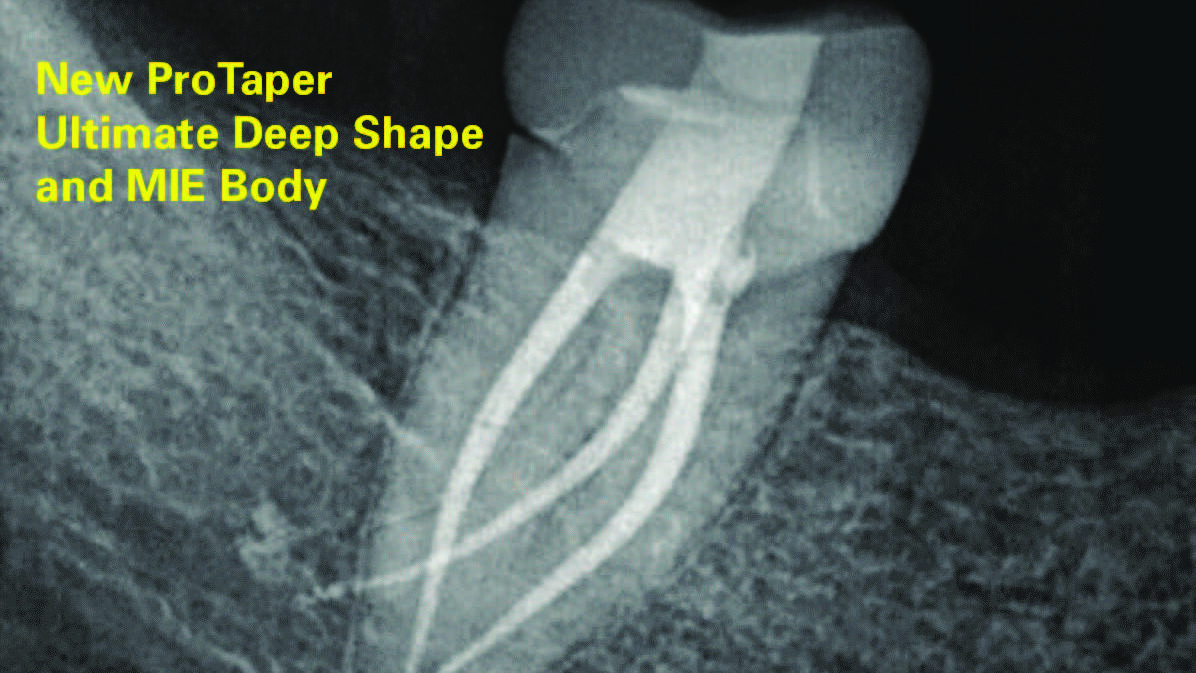

Deep Shape in Endodontics: Significance, Rationale and Benefit

The goal of endodontic treatment is to prevent or cure, when present, Lesions of Endodontic Origin, at times referred to as apical periodontitis. The role of bacteria in the pathogenesis of endodontic disease is well established, and therefore, it is critical to eradicate these pathogens by employing the highest level of presently developed standards. This … Read more